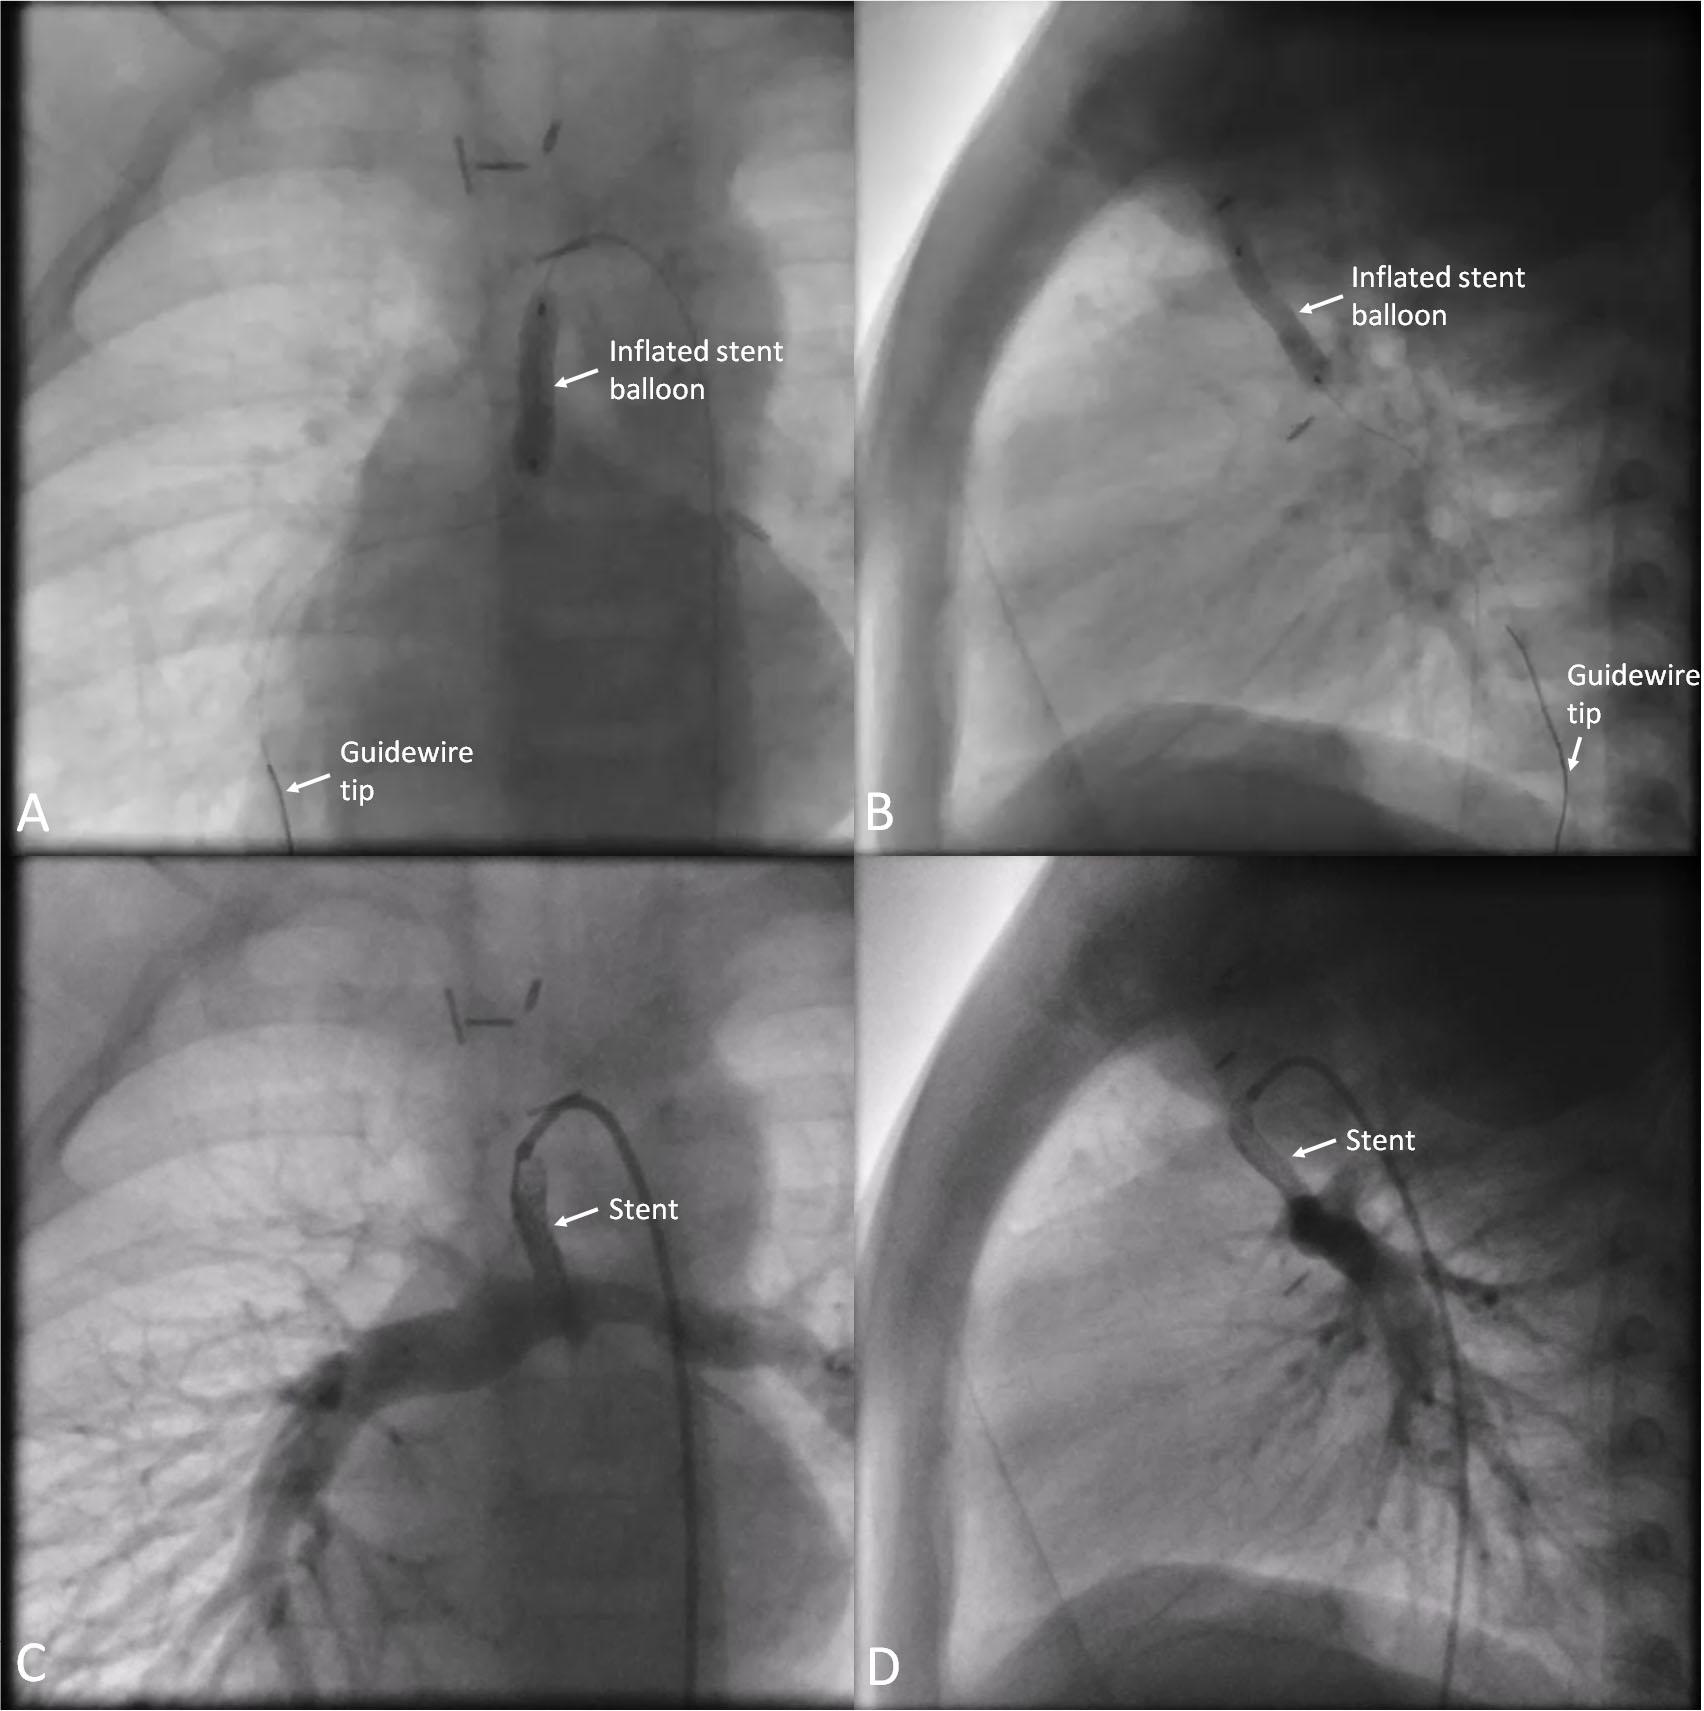

Figure 4